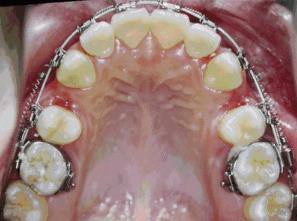

拔牙矯治會導(dǎo)致松動?

有時必須拔牙才有足夠空間重新排列牙齒

有的患者認(rèn)為拔了牙,牙齒缺失后,會出現(xiàn)牙齒松動的現(xiàn)象。德倫口腔矯治專家指出,對于一些錯合畸形,拔牙是必要的治療手段,例如牙齒嚴(yán)重擁擠,需要拔除相對不重要的牙齒(譬如第一雙尖牙),利用拔牙空出的間隙,才能把擁擠的牙齒排整齊;嚴(yán)重前突的牙齒,例如大齙牙等,通過正畸可將牙齒往里收,需要利用拔牙后的間隙才能更好地改善面型。

▲紅圈所示,牙合面有兩個尖叫做雙尖牙

▲嚴(yán)重的牙列擁擠或齙牙,一般都需要拔牙矯正